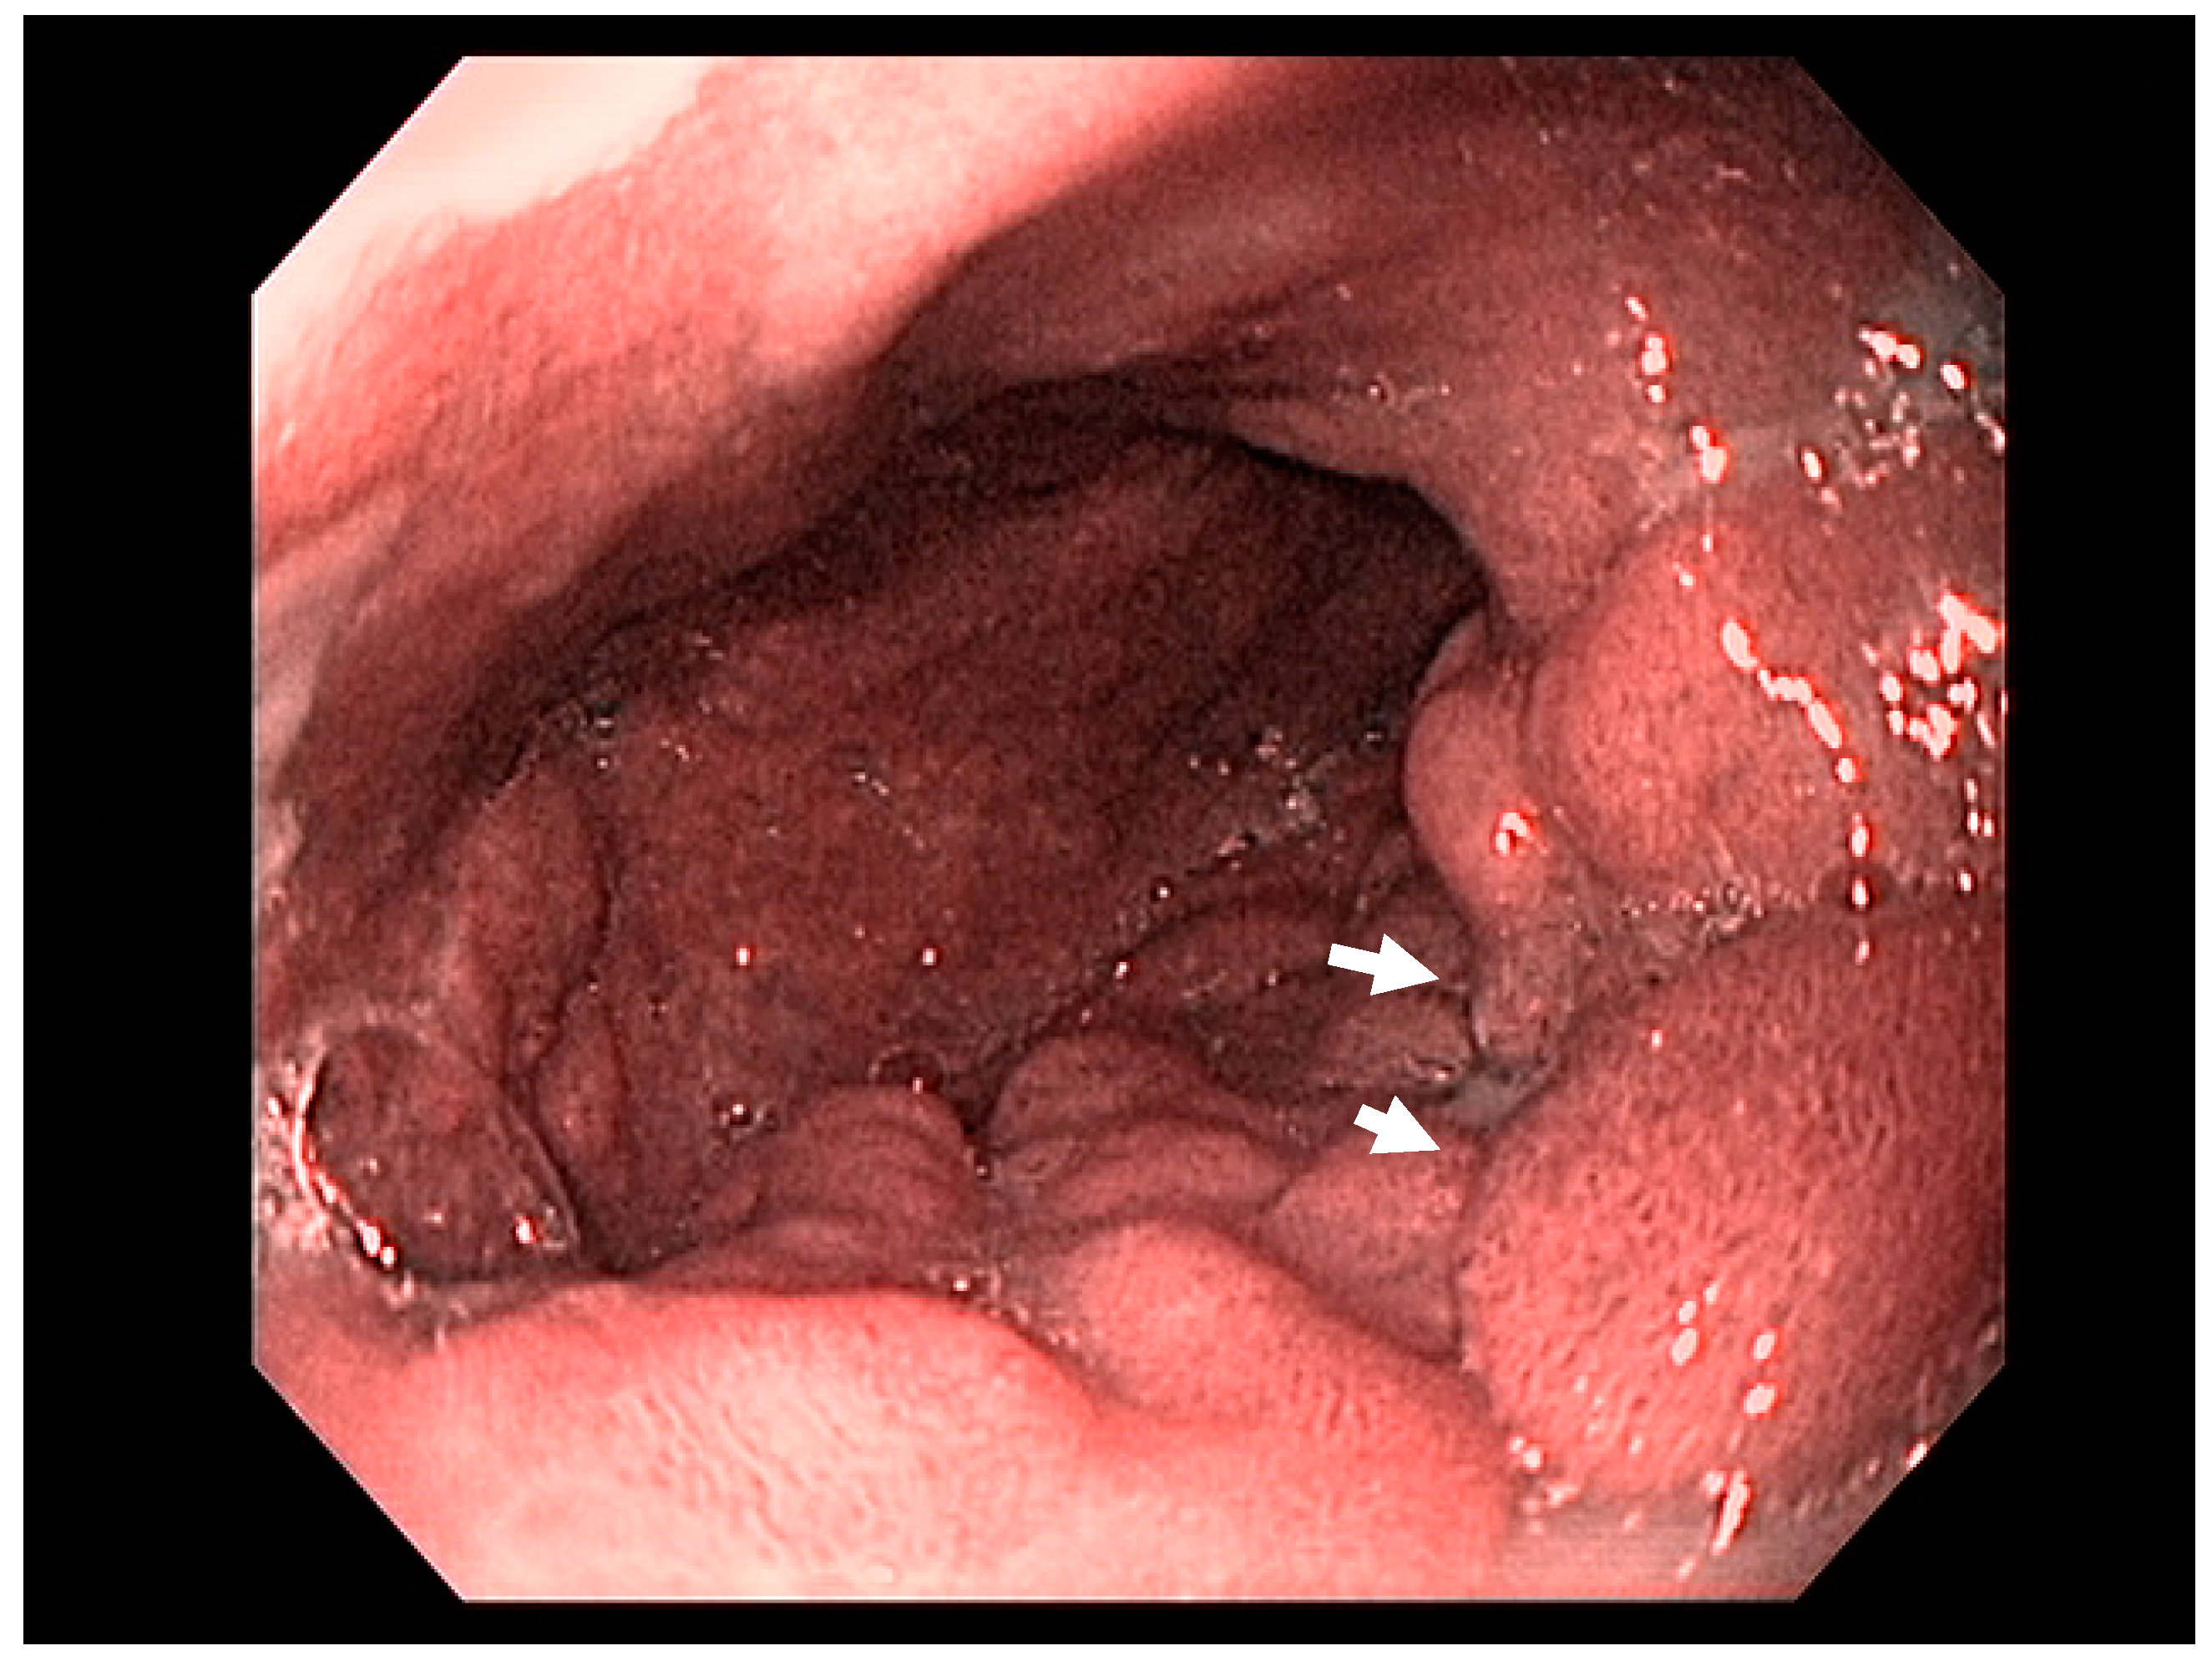

4.6. Gastric Lymphoma

4.7. Staging

- El-Zahabi, L.M.; Jamali, F.R.; El-Hajj, I.I.; Naja, M.; Salem, Z.; I Shamseddine, A.; El Saghir, N.S.; Zaatari, G.; Geara, F.; Soweid, A.M. The value of EUS in predicting the response of gastric mucosa–associated lymphoid tissue lymphoma to Helicobacter pylori eradication. Gastrointest. Endosc. 2007, 65, 89–96. [Google Scholar] [CrossRef] [PubMed]